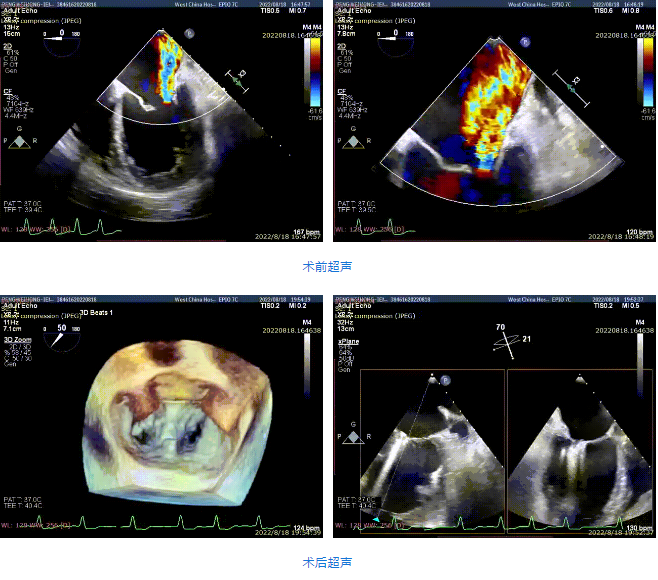

接受治療的是一例59歲男性患者,主訴“心累氣促5余年,加重伴胸痛1個多月”,已經(jīng)過規(guī)范化藥物治療。術前超聲提示左心明顯增大,右心稍大。左室心尖部肌小梁增多。室間隔及左室后壁厚度正常,左室后下壁基底段變薄、稍向外膨出,搏幅明顯減弱,余室壁搏幅減低,左室壁整體運動欠協(xié)調(diào)。二尖瓣瓣尖稍增厚,回聲稍增強,后瓣受牽拉,活動度差,前瓣關閉錯位,開放尚可。多普勒提示:二尖瓣大量反流(VC=6*18mm,EOA=0.53cm2,Vol=61ml);二尖瓣環(huán)舒張期運動頻譜呈單峰,EF=30%。

手術采用全身麻醉插管,經(jīng)股靜脈-房間隔入路,在TEE和DSA引導下完成房間隔穿刺。置入瓣膜夾系統(tǒng)后,在左房調(diào)整瓣膜夾的位置和軸向,后進入左室,在TEE引導下捕捉二尖瓣前后瓣葉,并關閉瓣膜夾。經(jīng)TEE反復確認手術效果后最終鎖定并釋放瓣膜夾。術后即刻超聲顯示瓣膜夾位置穩(wěn)定,功能良好,肺靜脈逆流和左房壓都明顯好轉。